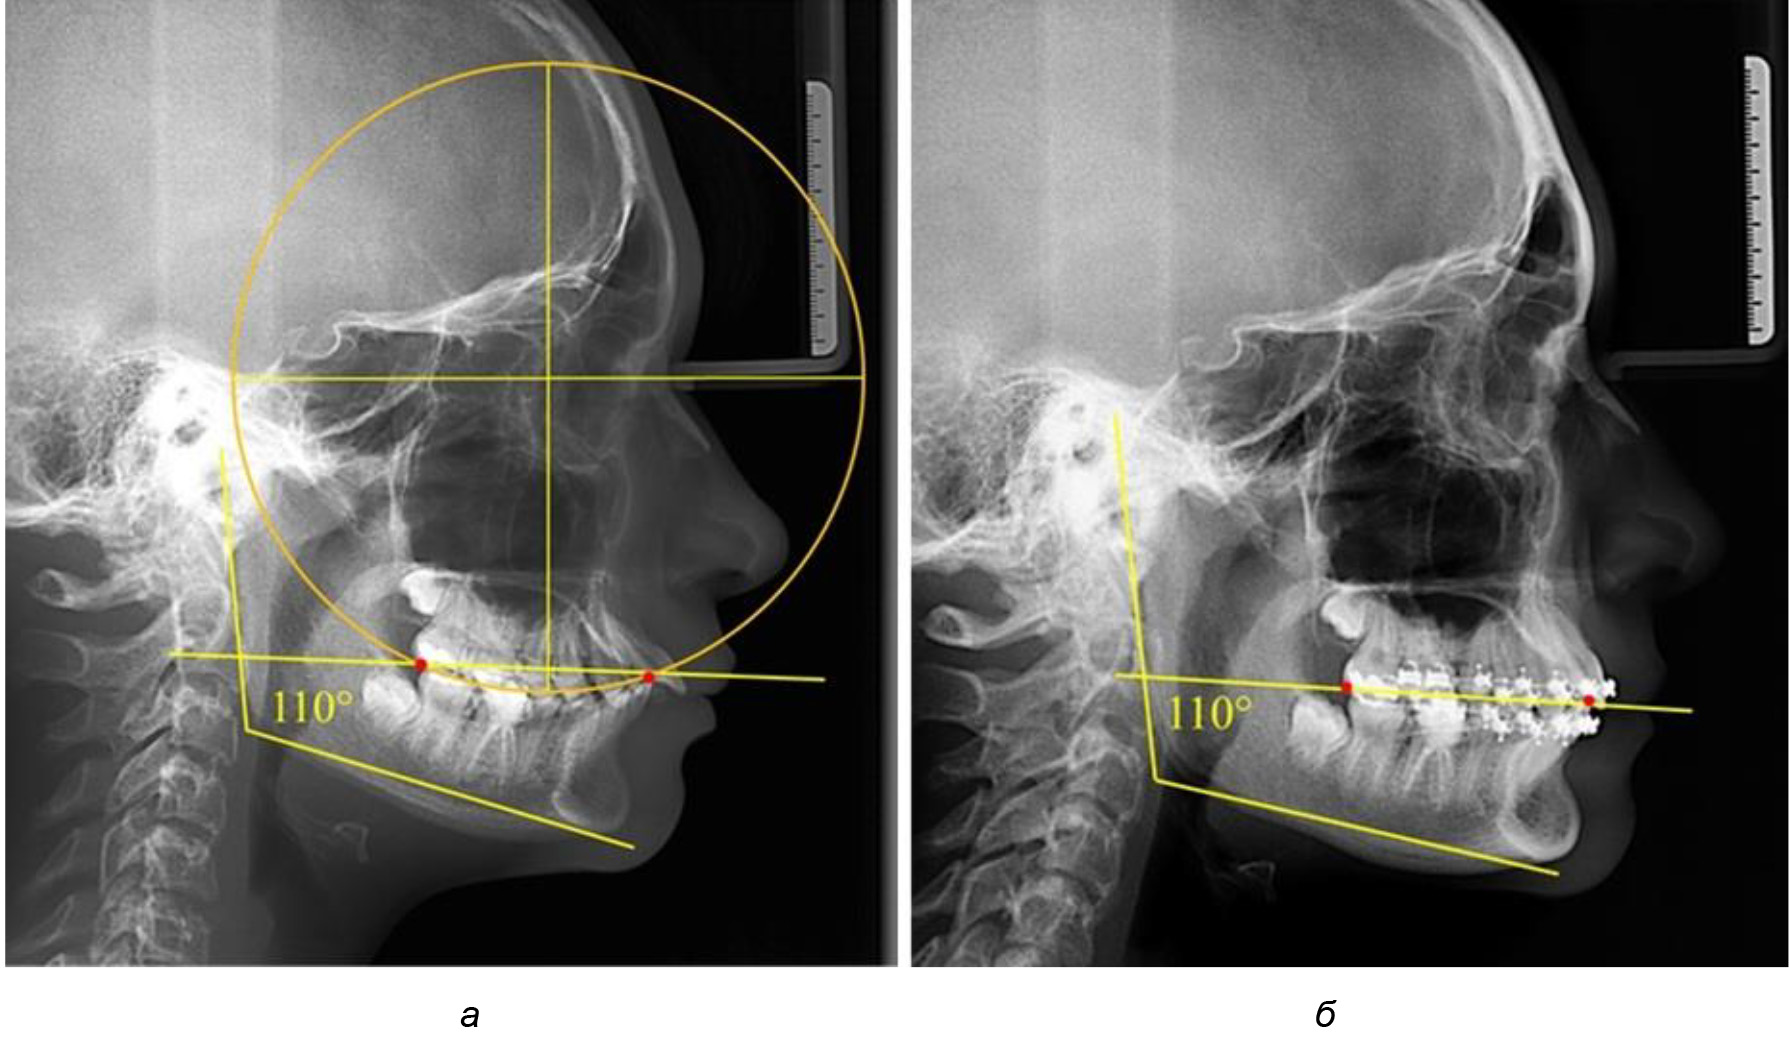

Глубина кривой Spee в среднем по 2-й подгруппе составила (5,69 ± 1,57) мм, что было достоверно больше, чем у людей с физиологической окклюзией (р ˂ 0,05). Достоверных различий с показателями, полученными при анализе ТРГ и ОПТГ, нами не отмечено (р ˃ 0,05). Отношение радиуса окружности к сагиттальному размеру окклюзионной линии в среднем по подгруппе составляло 1,372 ± 0,042 и не соответствовало числу Фибоначчи, что может быть использовано в качестве диагностического критерия определения патологической формы кривой Spee. После лечения пациентов техникой «прямой» дуги было отмечено незначительное увеличение сагиттального размера окклюзионной лини в среднем на (2,12 ± 0,77) мм. Однако окклюзионная линия практически касалась окклюзионного контура всех жевательных зубов, и отмечалось практически полное отсутствие кривой Spee.

Таким образом, проведенное лечение техникой «прямой» дуги способствует нормализации окклюзионного равновесия и торку передних зубов, однако не соответствует оптимальному окклюзионному статусу, характеризующему физиологическую окклюзию. При этом величина нижнечелюстного угла оставалась на прежнем уровне (рис. 5).

Рис. 5. Особенности ТРГ при патологической кривой Spee до лечения (а) и после лечения (б) техникой «прямой» дуги

Обращает на себя внимание, что глубина кривой Spee в анализируемой подгруппе практически не отличалась от показателей, полученных у людей с физиологической окклюзией, и составляла (4,23 ± 1,58) мм. Отношение радиуса окружности к сагиттальному размеру окклюзионной линии в среднем по подгруппе составляло 1,623 ± 0,02 и соответствовало числу Фибоначчи.

После лечения пациентов техникой «прямой» дуги, так же как и в 1-й подгруппе, было отмечено увеличение сагиттального размера окклюзионной лини в среднем на (2,38 ± 0,83) мм. Окклюзионная линия практически касалась окклюзионного контура всех жевательных зубов, и отмечалось практически полное отсутствие кривой Spee, так же как и у людей 1-й подгруппы 2-й группы (рис. 6).

Рис. 6. Особенности ТРГ при оптимальной кривой Spee до лечения (а) и после лечения (б) техникой «прямой» дуги

Таким образом, проведенное лечение техникой «прямой» дуги способствует нормализации окклюзионного равновесия и торку передних зубов, однако не соответствует оптимальному окклюзионному статусу, характеризующему физиологическую окклюзию. При этом величина нижнечелюстного угла оставалась на прежнем уровне.